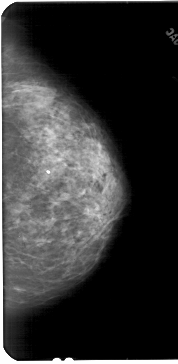

A_1842_1.RIGHT_MLO

RIGHT_MLO LINES 5491 PIXELS_PER_LINE 2821 BITS_PER_PIXEL 12 RESOLUTION 43.5 NON_OVERLAY